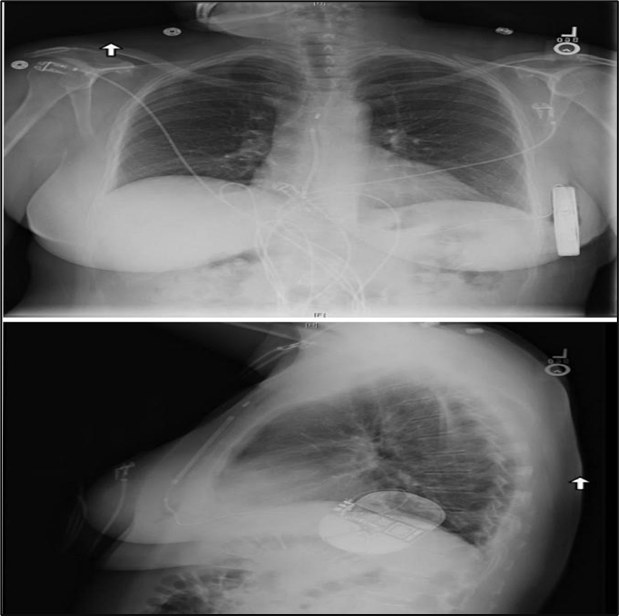

Figure No.3: the subcutaneous implantable cardioverter-defibrillator is implanted in the left lateral thoracic around the fifth and sixth intercostal space and near the mid-axillary line. the defibrillation coil is positioned parallel to the sternum and should ideally be in contact with the deep fascia.